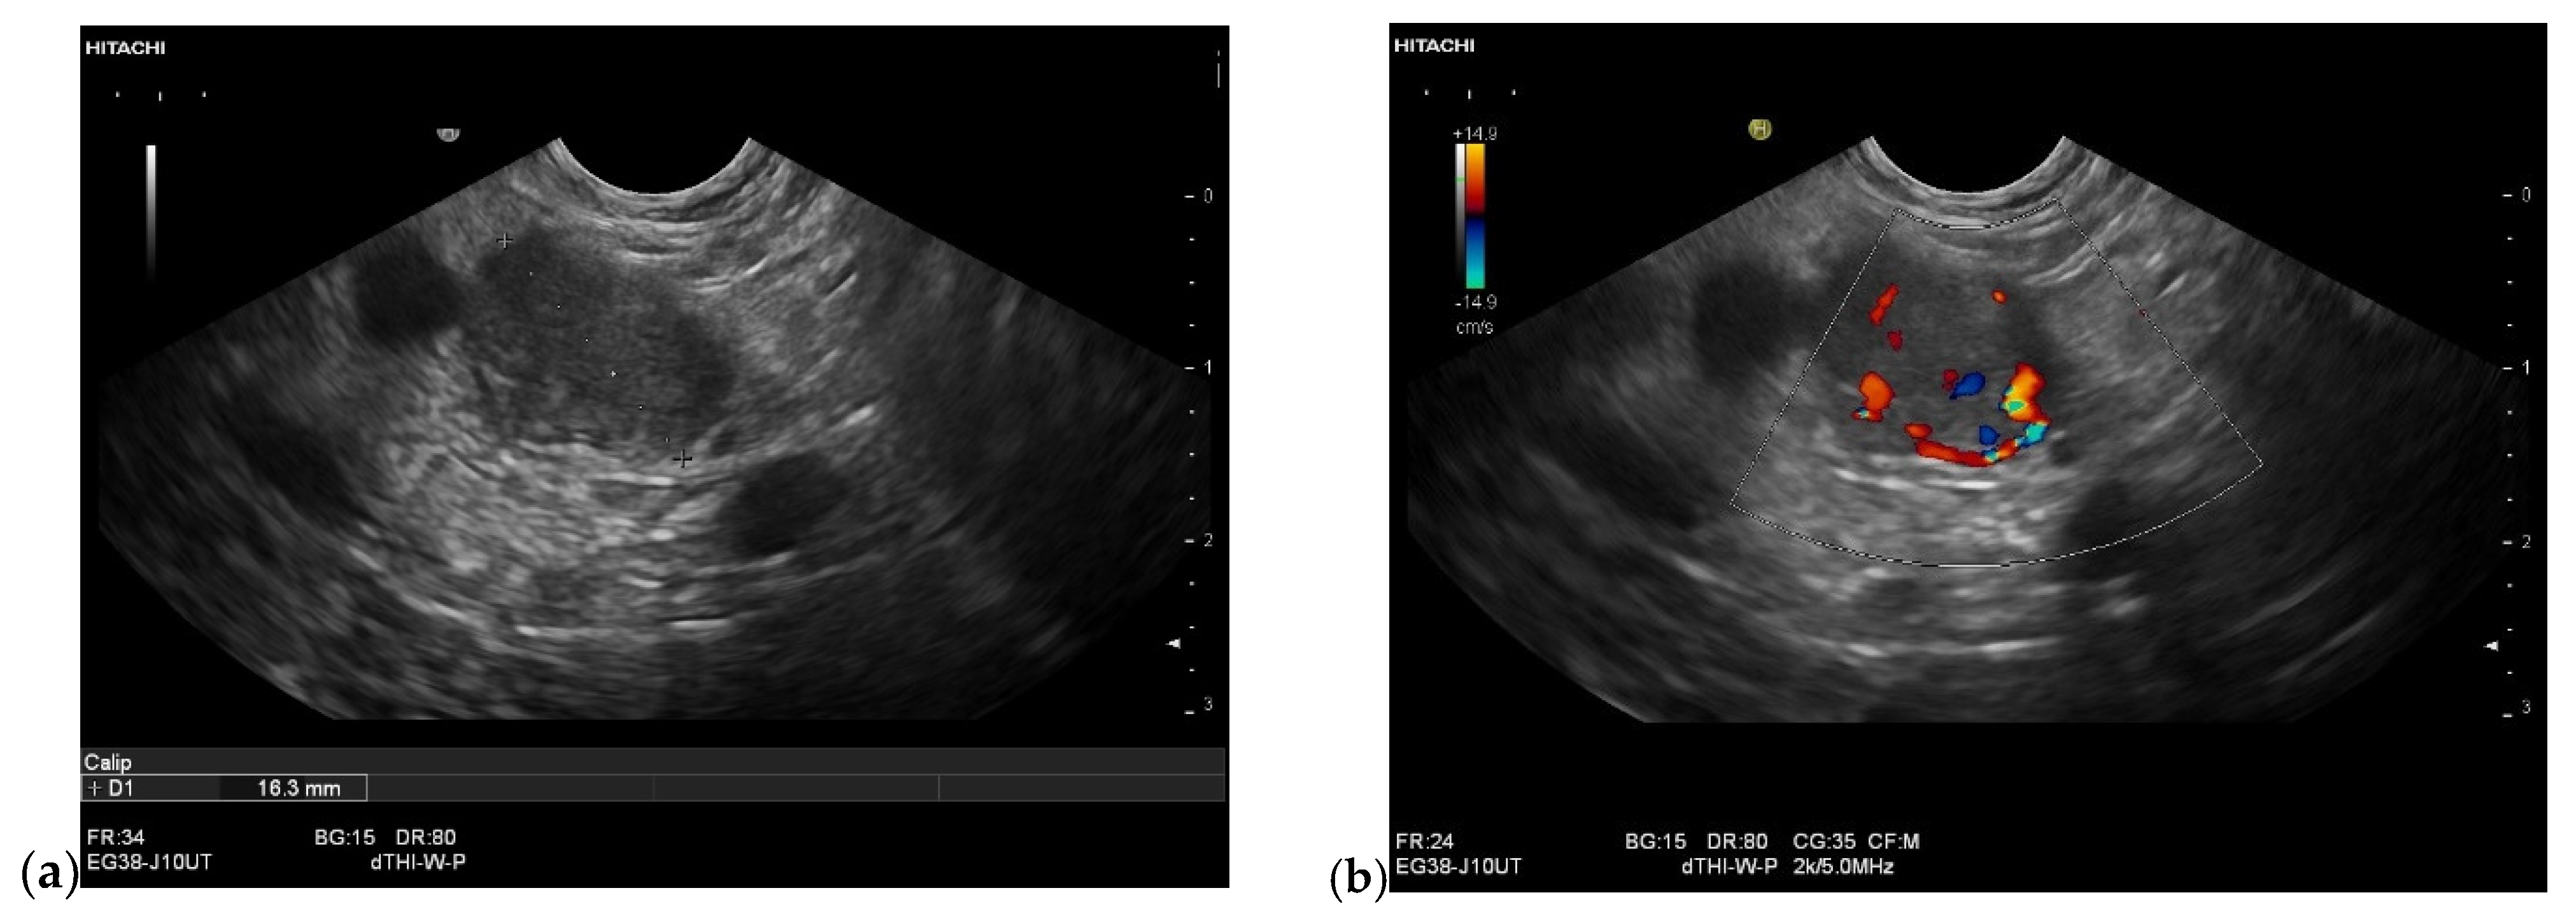

3.4. CEUS and CH-EUS

| Colour Doppler Imaging | RCC metastases are hypervascularized Most other pancreatic metastases are hypovascularized | No hypervascularization | Hypervascularized |

| RCC metastases [83] (n = 4) | Hyperenhancement, Early | Hyperenhancement | ||

| RCC metastases [61] (n = 3) | Hyperenhancement, homogeneous pattern | Slow washout | ||

| RCC metastasis [86] (n = 1) | Hyperenhancement, Inhomogeneous pattern | No washout | ||